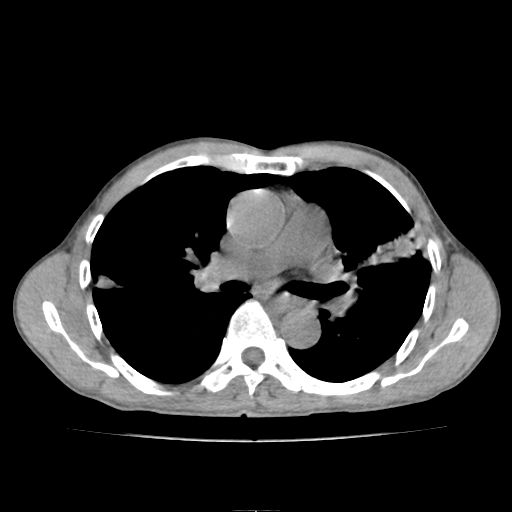

标题: CT25795:感冒后反复咳嗽两月余,痰中带血半月余。X诊断“肺 [打印本页]

标题: CT25795:感冒后反复咳嗽两月余,痰中带血半月余。X诊断“肺

1.双肺肺梗塞(理由:病灶呈三角形,与胸膜相连且局部胸膜肥厚,左心室增大)伴肺感染。

肺梗塞虽然有创意,但不现实。我考虑感染性病灶。

支持双肺感染,建议治疗后复查。

考虑两肺感染性病变,左肺上叶舌段肿瘤性病变待排;建议抗炎治疗后复查。